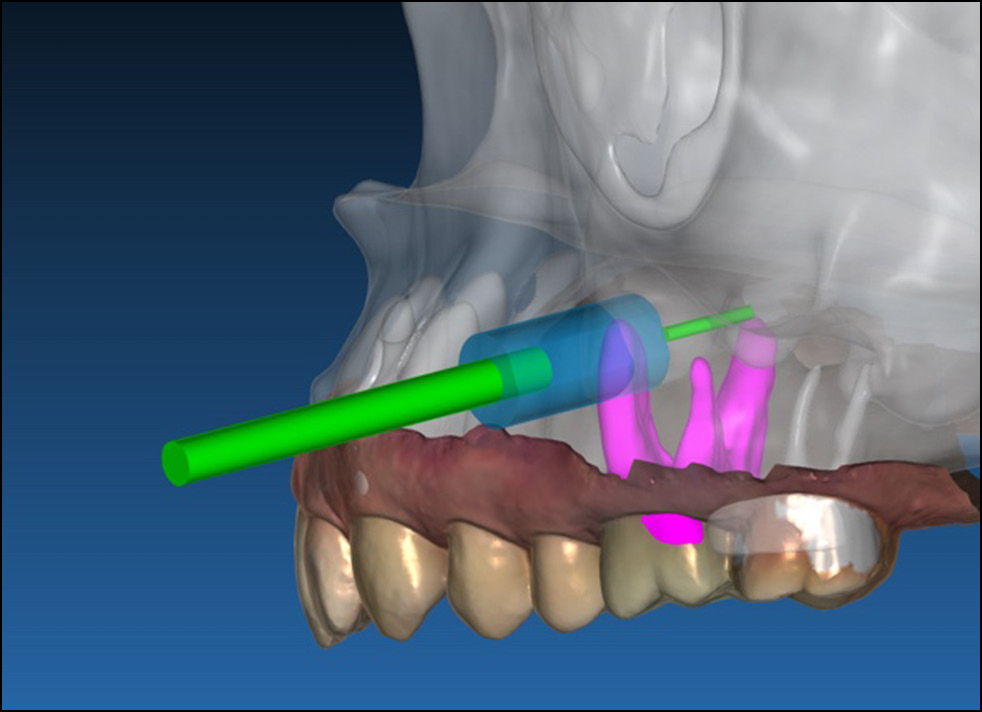

В программу загружали КЛКТ-изображения в формате DICOM и изображения, полученные методом оптического сканирования на предоперационном этапе. После совмещения DICOM- и STL-файлов хирург определял зону вмешательства и начинал построение 3D-проекции. Зона вмешательства представляет собой область, в которой локализованы новообразования, кисты или ретенированные зубы. В зоне вмешательства предусматривали достаточное расстояние до всех прилежащих анатомических структур, таких как нервы и корни зубов. Следующим шагом была сегментация зоны вмешательства. Сегментацию изображения выполняли вручную или полуавтоматически (рис. 13).

Рис. 13. Этап сегментации в программе Medgital Vision Editor (инородное тело в верхнечелюстной пазухе).

Полученный файл с сегментированной зоной вмешательства сохраняли в формате STL.

- Цифровое планирование хирургического доступа к зоне вмешательства. После сегментации зоны вмешательства хирург выбирал оптимальное местоположение хирургического доступа. Для этого использовали программу RealGuide 5.3, предназначенную для проведения операций по имплантации под визуализационным контролем. Однако вместо виртуальной установки зубного имплантата в требуемом положении виртуально помещали цилиндр, размер которого соответствовал внутреннему размеру трепанационного бора. Цилиндрический имплантат диаметром 5 мм виртуально устанавливали в месте планируемого хирургического доступа (рис. 14). В формате STL создавали и сохраняли виртуальный шаблон для сверления, обеспечивающий ориентацию трепанационного бора, наружный диаметр которого соответствовал цилиндрическому имплантату.

Рис. 14. Этап планирования хирургического доступа.

- Загрузка изображения хирургического доступа и 3D-изображения зоны вмешательства в AR-очки. Полученные изображения в формате STL загружали в AR-очки Microsoft HoloLens 2 с использованием программы Medgital Vision Editor.

- Проведение операции в AR-среде с учётом хирургического доступа и местоположения зоны вмешательства. При проведении операции использовали стерильную AR-метку. Метка была прикреплена к AR-держателю (подобного используемому при проведении КЛКТ). Метку 1 располагали в соответствии изображением сегментированного участка челюсти с выделенной визуализационной меткой. Во время хирургического вмешательства и после фиксации AR-метки проверяли калибровку положения метки и проекции сегментированных объектов челюсти. К наконечнику бормашины прикрепляли метку 2. Проекцию костного трепана ориентировали на метку 2. После запуска приложения с помощью голосовой команды на первом этапе выполняли регистрацию местоположения челюсти и наконечника. После регистрации изображения зоны вмешательства и хирургического доступа накладывали на изображение челюсти пациента. При перемещении наконечника через очки HoloLens 2 отслеживали каждое движение бора. Операция проводилась под местной анестезией (рис. 15).

Рис. 15. Хирургическое вмешательство в системе AR-навигации: а — этап регистрации; b — визуализация зоны вмешательства и хирургического доступа; c — визуализация хирургического доступа.